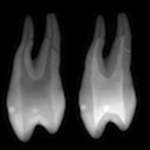

The convenient, "all-in-one" Endo Access Kit provides an economy of burs to initiate, progressively expand, and completely finish any access preparation.